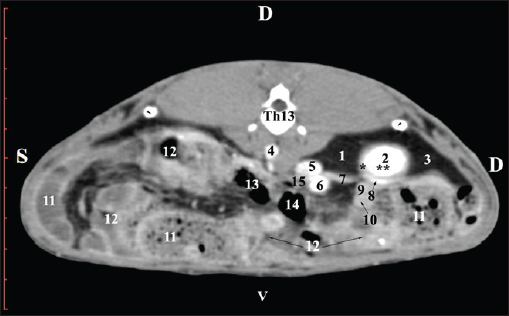

Fig. 1. Pre-contrast computed tomography (CT) anatomical scan of the regio abdominis cranialis at the Th13 level. (1) Lobus hepatis dexter; (2) ren dexter; (3) lobus caudatus (proc. caudatus) with visceral adipose tissue; (4) pars descendens of the duodenum; (5) ileum; (6) gl. adrenalis dextra; (7) colon ascendens; (8) cecum; (9) colon transversum; (10) colon descendens; (*) 13th rib. At the next scan level (L1), the normoattenuated image of the right kidney was more detailed and in contact with the lobus hepatis dexter, lobus caudatus, duodenal pars descendens, and ileum. The cortex renis and medulla renis were not clearly differentiated. Pelvis renalis appeared as a linear hypoattenuated finding against the relatively normoattenuated kidney cortex and medulla. The proximal part of the ureter was seen medial to the right kidney (Figs. 2 and 3).

Fig. 2. Pre-contrast computed tomography (CT) anatomical scan of the regio abdominis cranialis at the L1 level. (1) Ren dexter; (2) lobus hepatis dexter; (3) lobus caudatus (proc. caudatus) with visceral adipose tissue; (4) pars descendens of the duodenum; (5) ileum; (6) cecum; (7) colon ascendens; (8) colon transversum; (9) colon descendens; (10) jejunum.